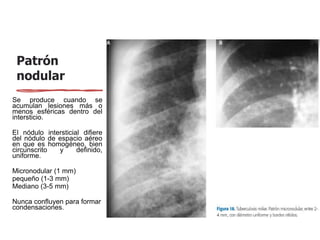

nodular

Se produce cuando se

acumulan lesiones más o

menos esféricas dentro del

intersticio.

El nódulo intersticial difiere

del nódulo de espacio aéreo

en que es homogéneo, bien

circunscrito y definido,

uniforme.

Micronodular (1 mm)

pequeño (1-3 mm)

Mediano (3-5 mm)

Nunca confluyen para formar

condensaciones.